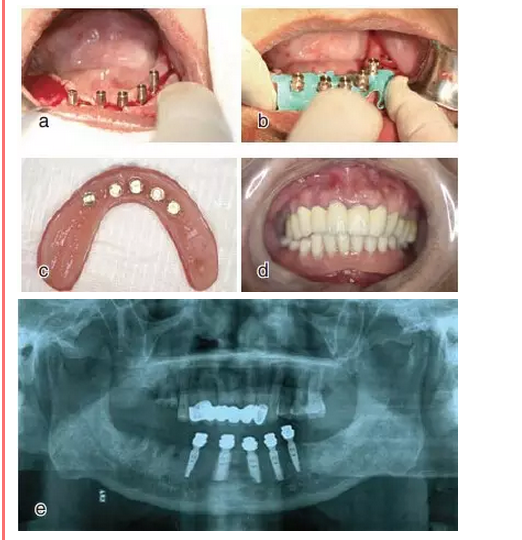

患牙21因根管治療超充,導(dǎo)致根尖周炎,唇側(cè)齲壞并出現(xiàn)瘺管。擬采用即刻種植修復(fù)。術(shù)前拍攝CBCT并做種植方案規(guī)劃,從方案上可知唇側(cè)及遠(yuǎn)中側(cè)骨缺損較為嚴(yán)重,需要同期進(jìn)行引導(dǎo)骨再生術(shù)(GBR)。

種植方案規(guī)劃:a.近遠(yuǎn)中方向的截面圖,唇側(cè)需要GBR;b.軸向截面圖;c. 模擬植入4.0×13 mm

的種植體

圖11 導(dǎo)板上備孔并植入植體,a.戴上導(dǎo)板,逐級(jí)備孔;b.植入種植體,并旋入覆蓋螺絲

進(jìn)行引導(dǎo)骨再生(GBR)術(shù),在骨缺損區(qū)填入骨粉,并在植骨區(qū)覆蓋人工骨膜,然后進(jìn)行嚴(yán)密縫合(圖12)。注意填入的骨粉應(yīng)該壓實(shí),人工骨膜要完整覆蓋植骨區(qū),縫合時(shí)需要進(jìn)行無(wú)張力嚴(yán)密縫合,在做切口時(shí)應(yīng)設(shè)計(jì)減張切口。

永久修復(fù)后3年進(jìn)行回訪,種植體骨結(jié)合穩(wěn)定,美學(xué)效果良好。